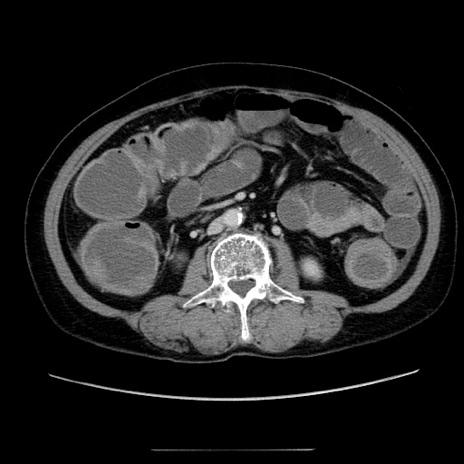

症例5(横断像)

【症例】70歳代女性

【主訴】お腹が張る

【現病歴】1週間くらい前から腹部膨満の自覚あり。昨日夜から増悪したため、本日救急外来受診。

【身体所見】意識清明、BT 36.5℃、BP 165/106mmHg、HR 80bpm、SpO2 98%、腹部:膨満、軟、自発痛・圧痛なし、触診にて不快感あり、腸蠕動音:減弱

【データ】WBC 12600、CRP 1.04